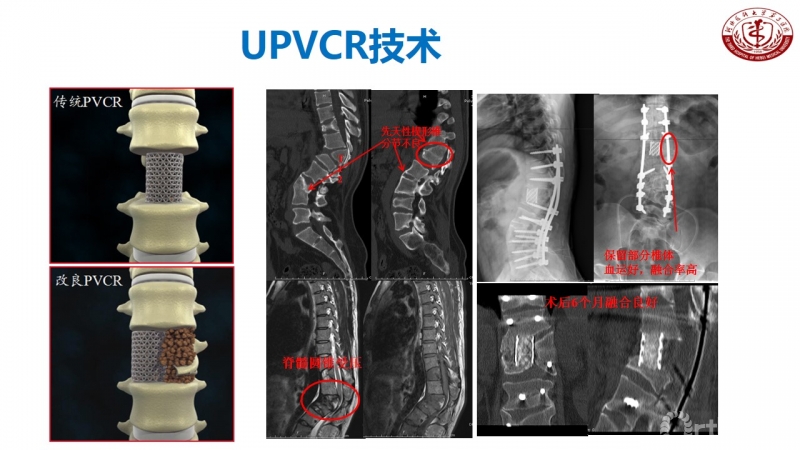

众所周知,脊椎结核后突畸形是结核病严重的后遗症之一。不仅影响患者外表仪容和心理,还可能出现晚发病灶造成截瘫。30多岁的小李就是一位脊柱结核后造成后凸畸形伴截瘫的患者,其畸形角度高达90度。针对此类患者的治疗大多就是截骨矫形,手术创伤大不说,椎体切除后造成的脊柱失稳等一系列后遗症也是令医生和患者担忧的。为解决临床上的这类问题,丁文元教授对传统的PVCR截骨技术进行了简化和改良,即后路单侧截骨部分椎体切除固定矫形术(UPVCR)入路,该技术采用后方单侧截骨,切除部分椎体、相邻椎间盘大部,保留对侧椎弓根及部分椎体,重建置入钛网支撑。随后,丁文元教授通过UPVCR技术对小李实施了手术,经过家人悉心地照顾,小李术后肌力恢复的良好,很快就出院了。三个月复查时竟是自己走路来的,临床疗效让患者及家人很是满意。

患者术前资料

患者术后资料

丁文元教授介绍说,UPVCR技术的优势在于手术操作简单,易于掌握,学习曲线短,手术时间短,出血少,神经并发症少;临床应用时极少发生断钉、断棒、不融合的现象,术中保留了良好的血运、植骨床,提供骨生长环境,保证部分骨支撑,术后极少发生矫正丢失,临床效果肯定。